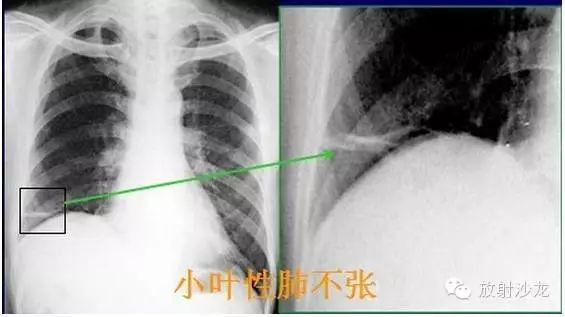

X線診斷要點 關於 肺不張 需要弄清楚以下幾點 每日頭條